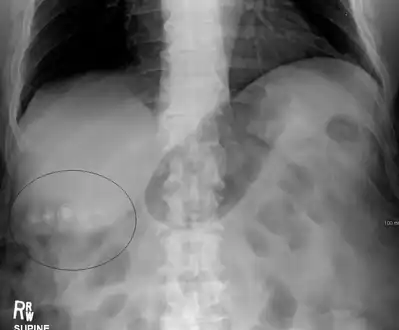

Mixed (brown pigment stones) typically contain 20–80% cholesterol (or 30–70%, according to the Japanese classification system).[36] Other common constituents are calcium carbonate, palmitate phosphate, bilirubin and other bile pigments (calcium bilirubinate, calcium palmitate and calcium stearate). Because of their calcium content, they are often radiographically visible. They typically arise secondary to infection of the biliary tract which results in the release of β-glucuronidase (by injured hepatocytes and bacteria) which hydrolyzes bilirubin glucuronides and increases the amount of unconjugated bilirubin in bile. Between 4% and 20% of stones are mixed.[3]

Diagnosis is typically confirmed by abdominal ultrasound. Other imaging techniques used are ERCP and MRCP. Gallstone complications may be detected on blood tests.[2]

On abdominal ultrasound, sinking gallstones usually have posterior acoustic shadowing. In floating gallstones, reverberation echoes (or comet-tail artifact) is seen instead in a clinical condition called adenomyomatosis. Another sign is wall-echo-shadow (WES) triad (or double-arc shadow) which is also characteristic of gallstones.[38]